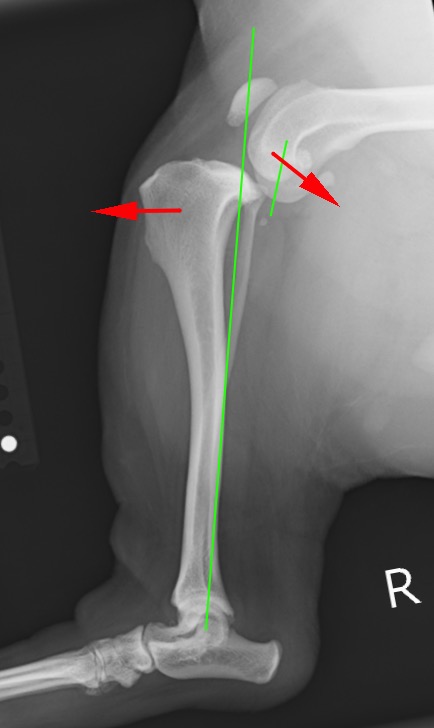

前十字靭帯を損傷した足。大腿骨と脛骨がずれてしまい体重がかけられない。